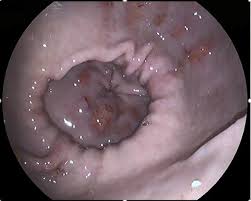

Les ulcères gastriques

chez le cheval